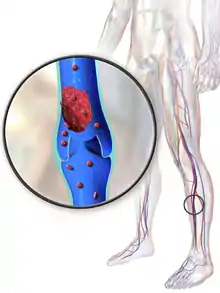

Deep vein thrombosis (DVT) is a type of venous thrombosis involving the formation of a blood clot in a deep vein, most commonly in the legs or pelvis.[9][lower-alpha 1] A minority of DVTs occur in the arms.[11] Symptoms can include pain, swelling, redness, and enlarged veins in the affected area, but some DVTs have no symptoms.[1] The most common life-threatening concern with DVT is the potential for a clot to embolize (detach from the veins), travel as an embolus through the right side of the heart, and become lodged in a pulmonary artery that supplies blood to the lungs. This is called a pulmonary embolism (PE). DVT and PE comprise the cardiovascular disease of venous thromboembolism (VTE).[2] About two-thirds of VTE manifests as DVT only, with one-third manifesting as PE with or without DVT.[12] The most frequent long-term DVT complication is post-thrombotic syndrome, which can cause pain, swelling, a sensation of heaviness, itching, and in severe cases, ulcers.[5] Recurrent VTE occurs in about 30% of those in the ten years following an initial VTE.[3]

Symptoms classically affect a leg and typically develop over hours or days,[20] though they can develop suddenly or over a matter of weeks.[21] The legs are primarily affected, with 4–10% of DVT occurring in the arms.[11] Despite the signs and symptoms being highly variable,[5] the typical symptoms are pain, swelling, and redness. However, these symptoms might not manifest in the lower limbs of those unable to walk.[22] In those who are able to walk, DVT can reduce one's ability to do so.[23] The pain can be described as throbbing and can worsen with weight-bearing, prompting one to bear more weight with the unaffected leg.[21][24] Additional signs and symptoms include tenderness, pitting edema (see image), dilation of surface veins, warmth, discoloration, a "pulling sensation", and even cyanosis (a blue or purplish discoloration) with fever.[5][20][21] DVT can also exist without causing any symptoms.[22] Signs and symptoms help in determining the likelihood of DVT, but they are not used alone for diagnosis.[19]